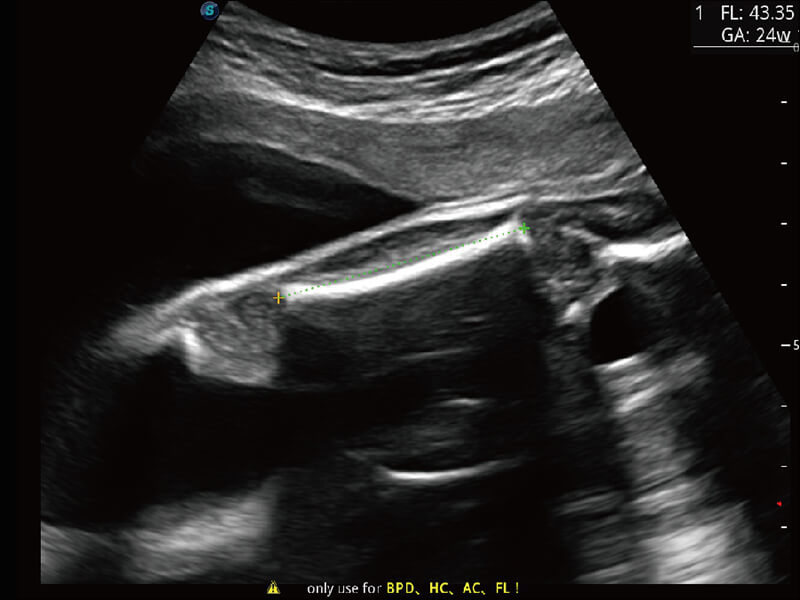

成像功能

S60探头工艺,从前端信号处理每一个环节采集无损声学数据,真实还原组织原貌,再现解剖细节。